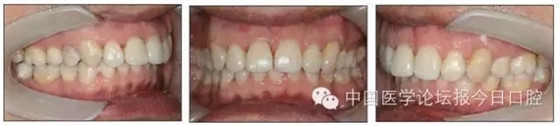

本病例為慢性牙周炎致前牙漂移、深覆(牙合)患者。本病例采用無托槽隱形矯治技術(shù)進行治療。無托槽隱形矯治器具有可摘戴、便于口腔衛(wèi)生維護和牙周治療的優(yōu)點,更適合于伴有牙周炎的錯(牙合)畸形患者的治療。 患者男,48歲,前牙有縫、前突求診。 患者面部對稱,側(cè)面觀上頜前突,下頜后縮。 口內(nèi)情況:恒牙列,24、34、44缺失,磨牙Ⅲ類關(guān)系,上牙列散隙,上前牙扇形漂移。前牙深覆(牙合)、深覆蓋??谇恍l(wèi)生較差,11與12間牙齦乳頭紅腫,多個牙探診有牙周袋形成,11松動Ⅰ度,余切牙松動(-),患者面像及口內(nèi)像如圖1、2所示。 圖1 治療前面像 圖2 治療前口內(nèi)像 全口曲面體層片(圖3)顯示,患者全牙列牙槽骨吸收;根尖片(圖4)示11近中牙槽骨角形吸收已達根尖1/3,21牙槽骨嵴頂吸收至根1/2,23牙槽骨近中骨板角形吸收至根1/2。磨牙區(qū)骨嵴頂吸收3mm。治療前頭顱側(cè)位片見圖3,治療前ODS模型見圖5。 圖4 治療前根尖片 圖5 治療前ODS模型 牙型:安氏Ⅲ類。骨型:Ⅱ類。面型:上頜前突,下頜后縮。 問題列表為:①上牙列間隙;②上切牙病理性牙移位;③前牙深覆(牙合)、深覆蓋;④24、34、44缺失;⑤慢性牙周炎。 矯治目標包括:①排齊牙列,關(guān)閉牙列間隙;②改善前牙深覆(牙合)、深覆蓋;③改善牙周狀況。 矯治設(shè)計有:①牙周基礎(chǔ)治療與維護。②壓低、內(nèi)收上切牙,關(guān)閉上牙列間隙。③壓低下切牙,伸長下后牙,整平Spee曲線,改善前牙覆(牙合)、覆蓋。 患者進行全口齦上潔治、齦下刮治,口腔衛(wèi)生宣教,并按牙周醫(yī)師的要求,每2~3個月行牙周檢查與治療。 牙周基礎(chǔ)治療結(jié)束3個月,開始隱形矯治。于14、25、35、36、45、46上粘接附件(圖6),于16、26(牙合)面粘接(牙合)墊。 圖6 ODS設(shè)計附件粘接圖示 矯治過程中注意(牙合)墊是否脫落或磨損,及時修補。 注意上前牙內(nèi)收時有無咬合干擾,及時調(diào)(牙合)。下頜前磨牙伸長到位后,磨除16、26(牙合)墊。 下頜佩戴第24步矯治器時,分別在36、37、46、47的頰、舌側(cè)粘接舌扣,矯治器上預(yù)留伸長空間,用3/16英寸、3.5盎司皮圈牽引,輔助伸長下磨牙(圖7)。 患者共戴用矯治器上頜32步,下頜26步。 矯治后,牙列間隙關(guān)閉,面型及覆(牙合)覆蓋改善。11根尖片(圖8)顯示,治療后較治療前,牙周支持組織增加,牙槽骨角形吸收區(qū)水平向縮小0.3mm,垂直向縮小0.6mm。11松動Ⅰ度,余切牙無松動。 圖8 治療后根尖片 圖9 治療后口內(nèi)像 圖10 治療后X線檢查 圖11 治療后ODS模型 正畸-牙周聯(lián)合治療對于牙周組織的影響 多學(xué)科綜合治療牙周炎患者不再是正畸治療的禁忌證。良好的牙周治療為正畸治療中的牙齒移動打下堅實基礎(chǔ),而正畸治療排齊牙齒、去除(牙合)干擾,有利于牙周健康。 牙周炎患者的正畸治療必須在牙周炎癥得到控制后才能進行,否則,菌斑會隨著牙齒的移動,特別是壓低而使牙周炎癥加重。牙周炎的正確診斷、牙周炎癥控制、正畸治療中和治療后的認真維護是治療成功的關(guān)鍵。根據(jù)臨床需要,一般每2~4周做一次潔治,每3個月進行牙周評估,同時患者必須進行非常良好的日??谇恍l(wèi)生維護。 固定矯治器使得牙周檢查、潔治和日??谇恍l(wèi)生維護變得困難,隱形矯治器可自行摘戴,便于患者日常維護和牙周治療,節(jié)約時間,提高菌斑控制效果。 有臨床研究表明,對于存在(牙合)創(chuàng)傷,伴有角形吸收的患牙,經(jīng)過牙周翻瓣手術(shù)控制住牙周炎癥后,使用正畸輕力壓低患牙,可以改善牙槽骨吸收的程度,并獲得一定程度的牙周新附著。本病例切牙壓低后,原來的牙槽骨吸收有改善。 病理性牙移位 病理性牙移位(PTM)在重度牙周炎患者中的發(fā)生率為30%~50%,且常見于上前牙區(qū)。其主要由于牙周支持組織喪失尤其是骨組織的丟失,咬合因素(如后牙缺失、前牙深覆牙合、牙合創(chuàng)傷等),頰舌唇肌力量不平衡及牙周和根尖周組織炎癥所致,是牙周炎患者要求正畸治療的主要原因之一。 PTM須通過正畸、牙周聯(lián)合,有時須配合修復(fù)才能達到理想的治療效果。正畸治療通常是壓低牙齒,臨床研究表明,牙周手術(shù)配合正畸壓低可以產(chǎn)生新附著,有利于PTM牙周組織的恢復(fù)。 本病例右上中切牙牙槽骨角形吸收,在盡量保證治療前后根尖片投照角度一致的情況下,以鄰牙作為校準,在根尖片上對治療前后的骨量進行評價,治療后牙槽骨角形吸收區(qū)水平向縮小0.3 mm,垂直向縮小0.6mm。盡管根尖片并不能說明骨量改變,但從影像學(xué)上能看到骨吸收區(qū)域有所減小。 無托槽隱形矯治器矯治牙周病的優(yōu)勢 無托槽隱形矯治器具有可摘戴、便于口腔衛(wèi)生維護和牙周治療的優(yōu)點,更適合于伴有牙周炎的錯(牙合)患者的治療;同時,無托槽隱形矯治器佩戴后具有牙弓夾板和(牙合)板的作用,可有效減少側(cè)向力,有利于牙周的恢復(fù)和減輕牙齒松動;由于無托槽隱形矯治器的設(shè)計是在三維數(shù)字模型上進行的,每個矯治器移動牙齒的數(shù)量和每個牙齒的移動距離可以得到量化控制,因而可以根據(jù)患者牙槽骨水平和對矯治力的耐受情況個性化設(shè)計矯治力,并且可以根據(jù)矯治中牙齒移動情況調(diào)整后續(xù)矯治器的設(shè)計。 有關(guān)磨牙伸長 單純使用無托槽隱形矯治器同步伸長后牙比較困難。該病例先使用磨牙(牙合)墊打開咬合,通過矯治器伸長前磨牙,在前磨牙建立咬合后,磨除磨牙上的(牙合)墊,通過輔助牽引伸長磨牙,最終達到伸長后牙、整平Spee曲線的目的。 史真,主任醫(yī)師,現(xiàn)任北京黃寺整形外科醫(yī)院口腔科主任,第四軍醫(yī)大學(xué)口腔正畸學(xué)碩士,為世界正畸醫(yī)師聯(lián)盟(WFO)會員、全軍口腔醫(yī)學(xué)專業(yè)委員會委員、中華口腔正畸專業(yè)委員會委員、中華醫(yī)學(xué)美學(xué)與美容學(xué)會齒科美容學(xué)組成員、北京口腔醫(yī)學(xué)會兒童口腔專業(yè)委員會常務(wù)委員、北京口腔醫(yī)學(xué)會正畸專業(yè)委員會委員、《中華醫(yī)學(xué)美學(xué)與美容》雜志審稿專家,是我國最早開展無托槽隱形矯治技術(shù)的口腔醫(yī)師之一。

圖12 保持半年后口內(nèi)像